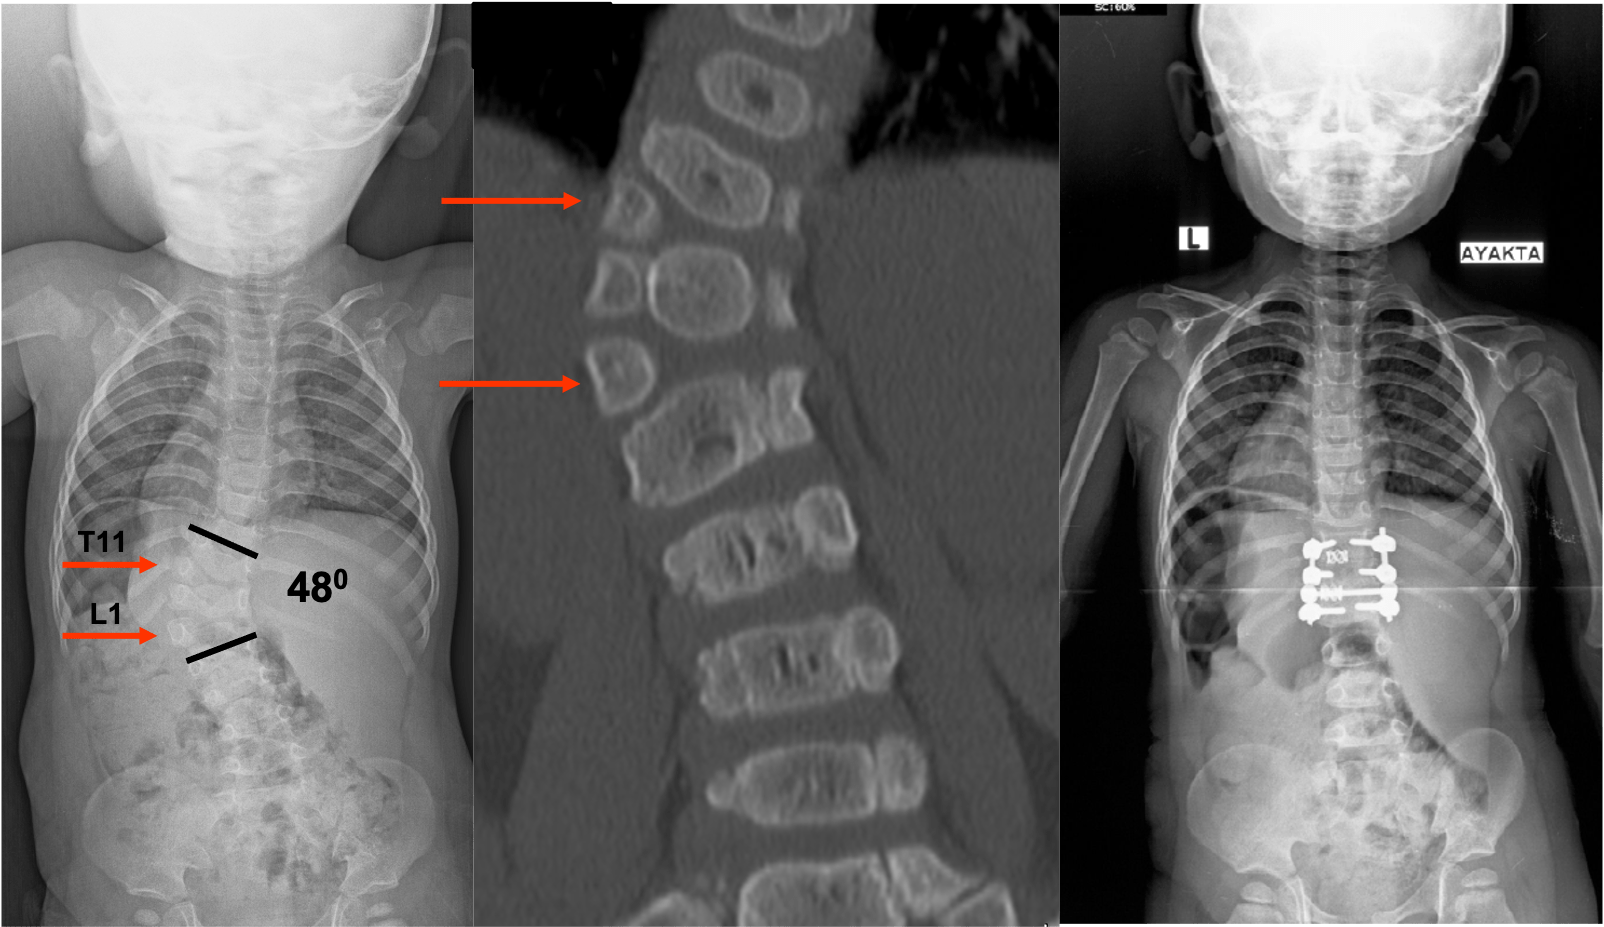

Сколиоз – это состояние, при котором позвоночник наклоняется в сторону. Врожденный сколиоз обычно замечаютв младенчестве. Однако его можно диагностировать во время беременности или сразу после рождения. Ранняя диагностика при сколиозе очень важна, поскольку она также определяет курс лечения. Если искривление не является тяжелым при диагностировании в младенчестве, ребенок находится под наблюдением. Сколиоз пытаются держать под контролем различными методами, пока ребенок не достигнет возраста, подходящего для оперативного вмешательства.